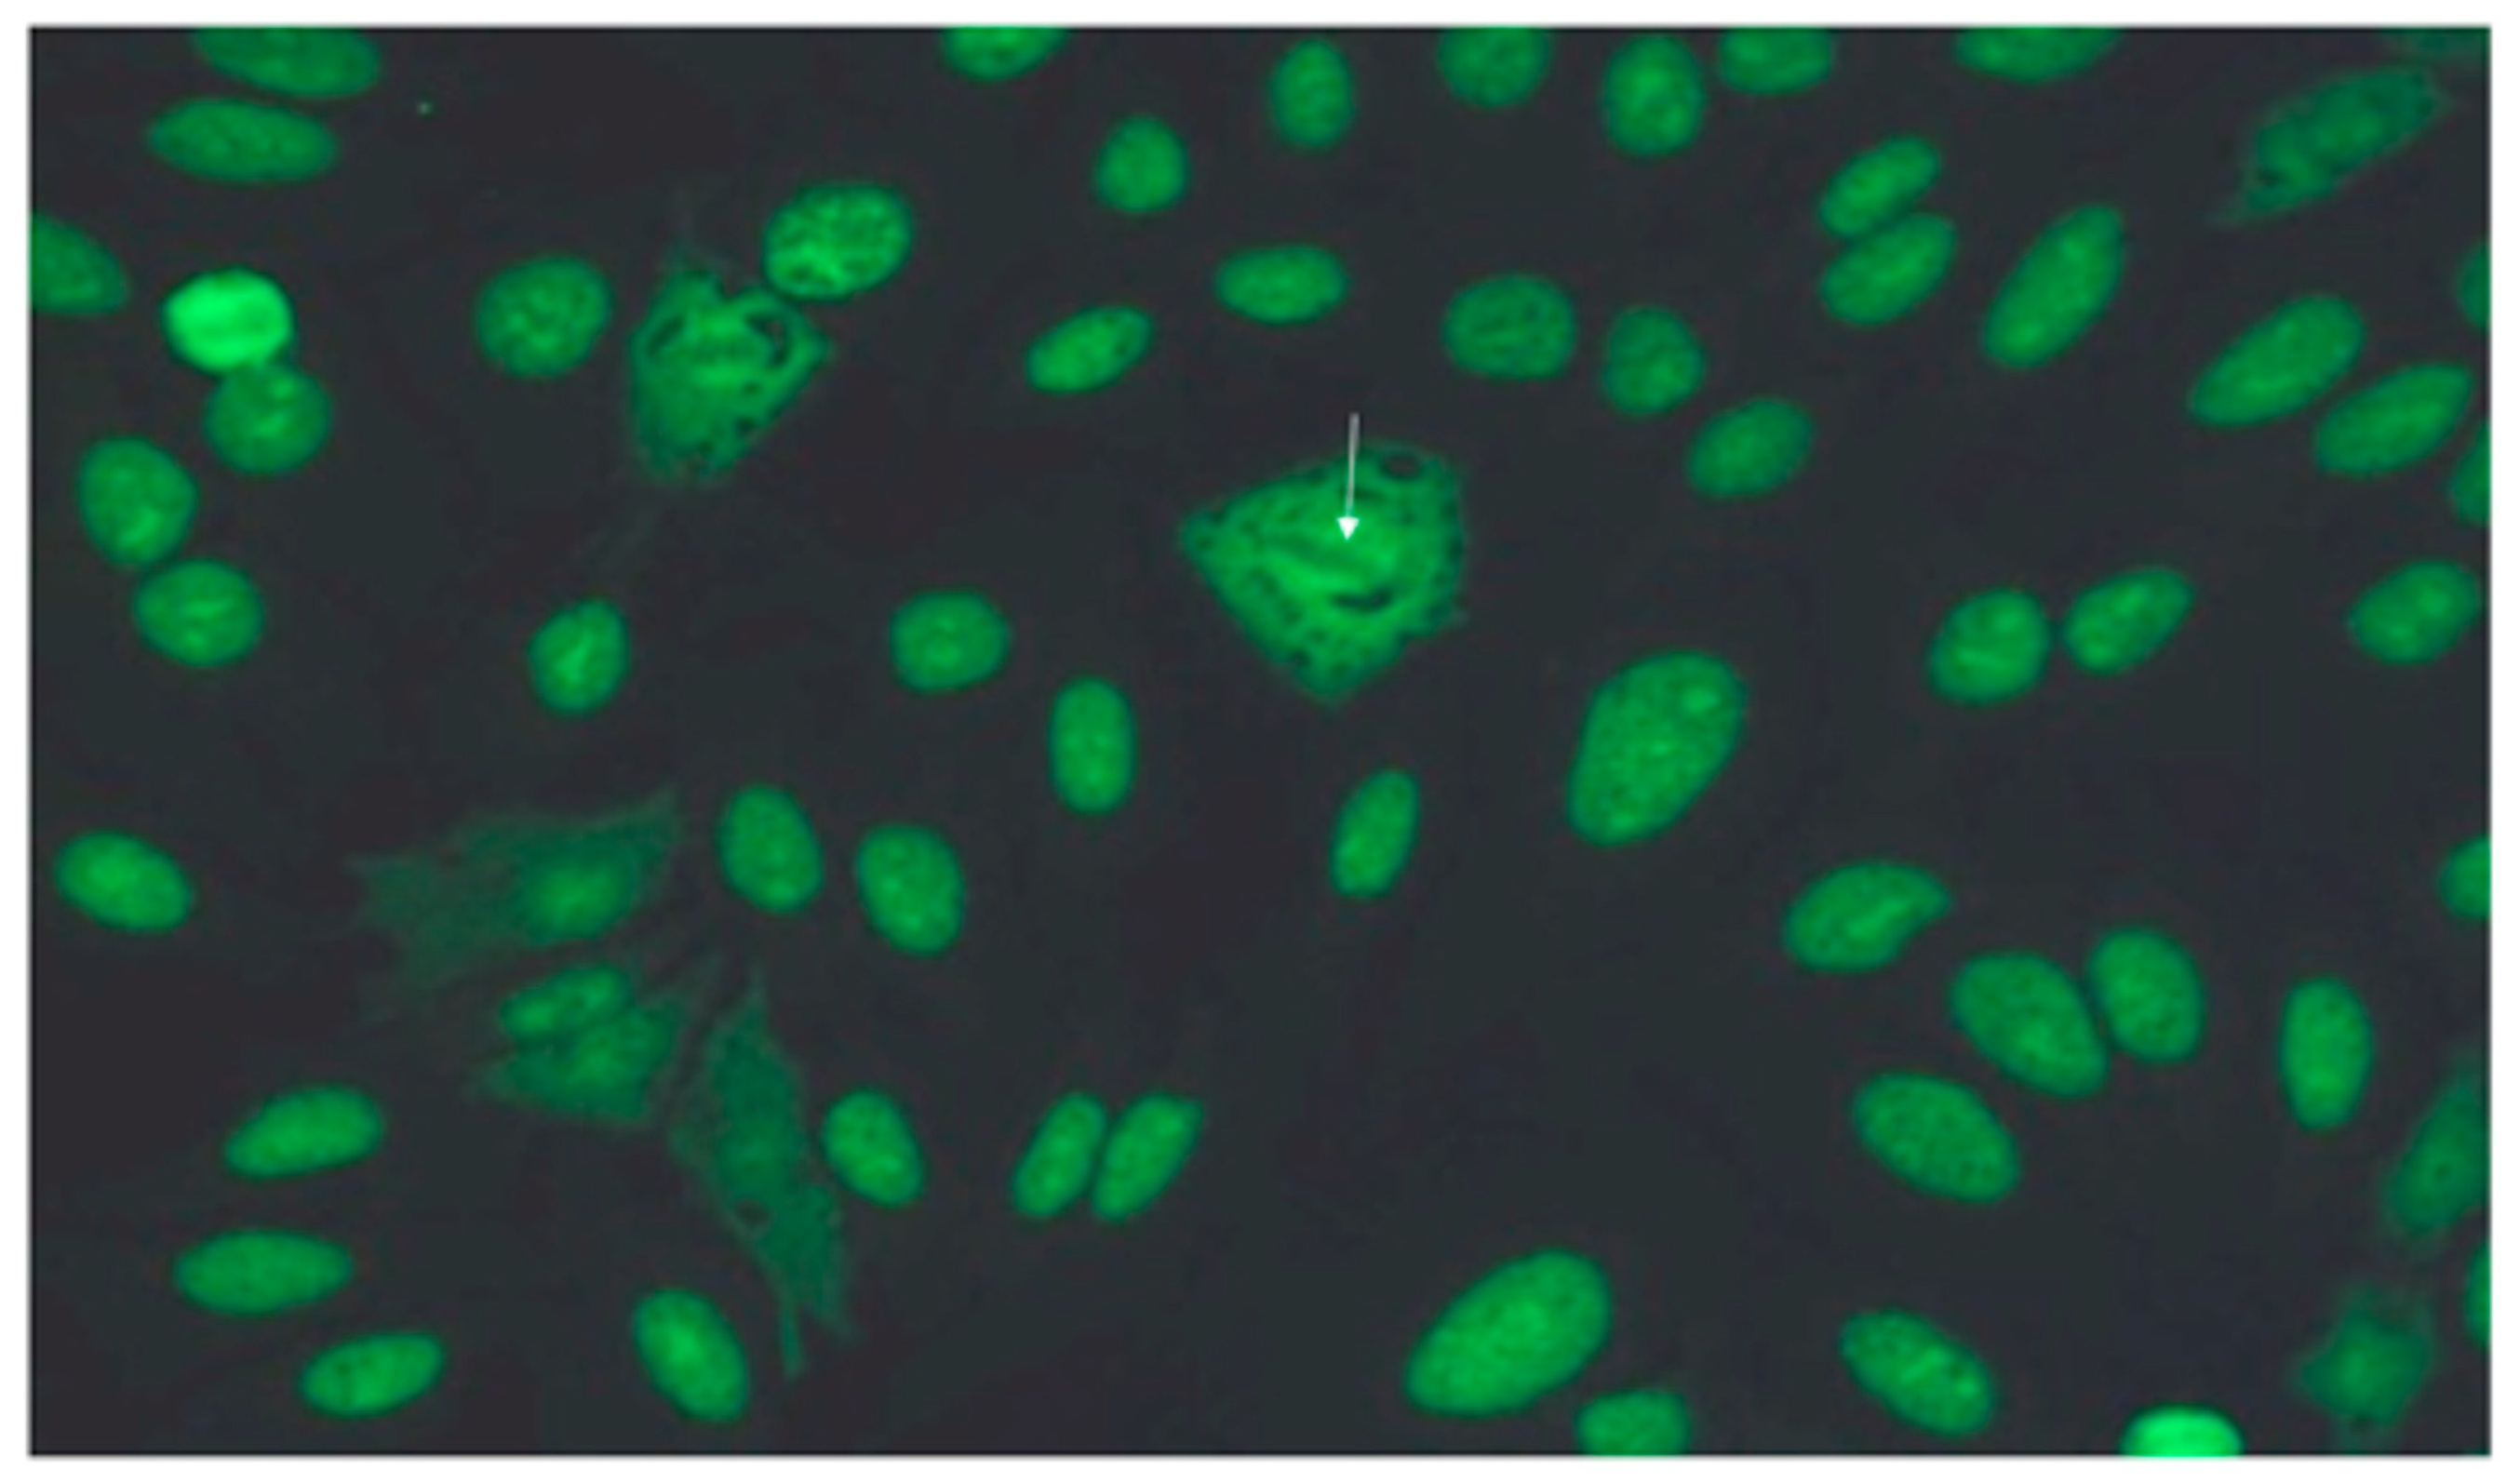

2.2. Antibody Testing

3.5. Pulmonary Function Tests